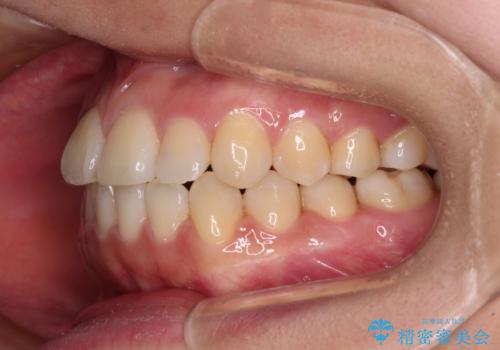

反対咬合とクロスバイトを改善して噛みやすい咬合に

骨格的に下顎が前方位の受け口傾向であり、それが原因でクロスバイトとなっていました。

なお、右奥の歯が180度回転した状態で萌出しており、こちらは改善困難なため、そのままの向きで配列することとしました。